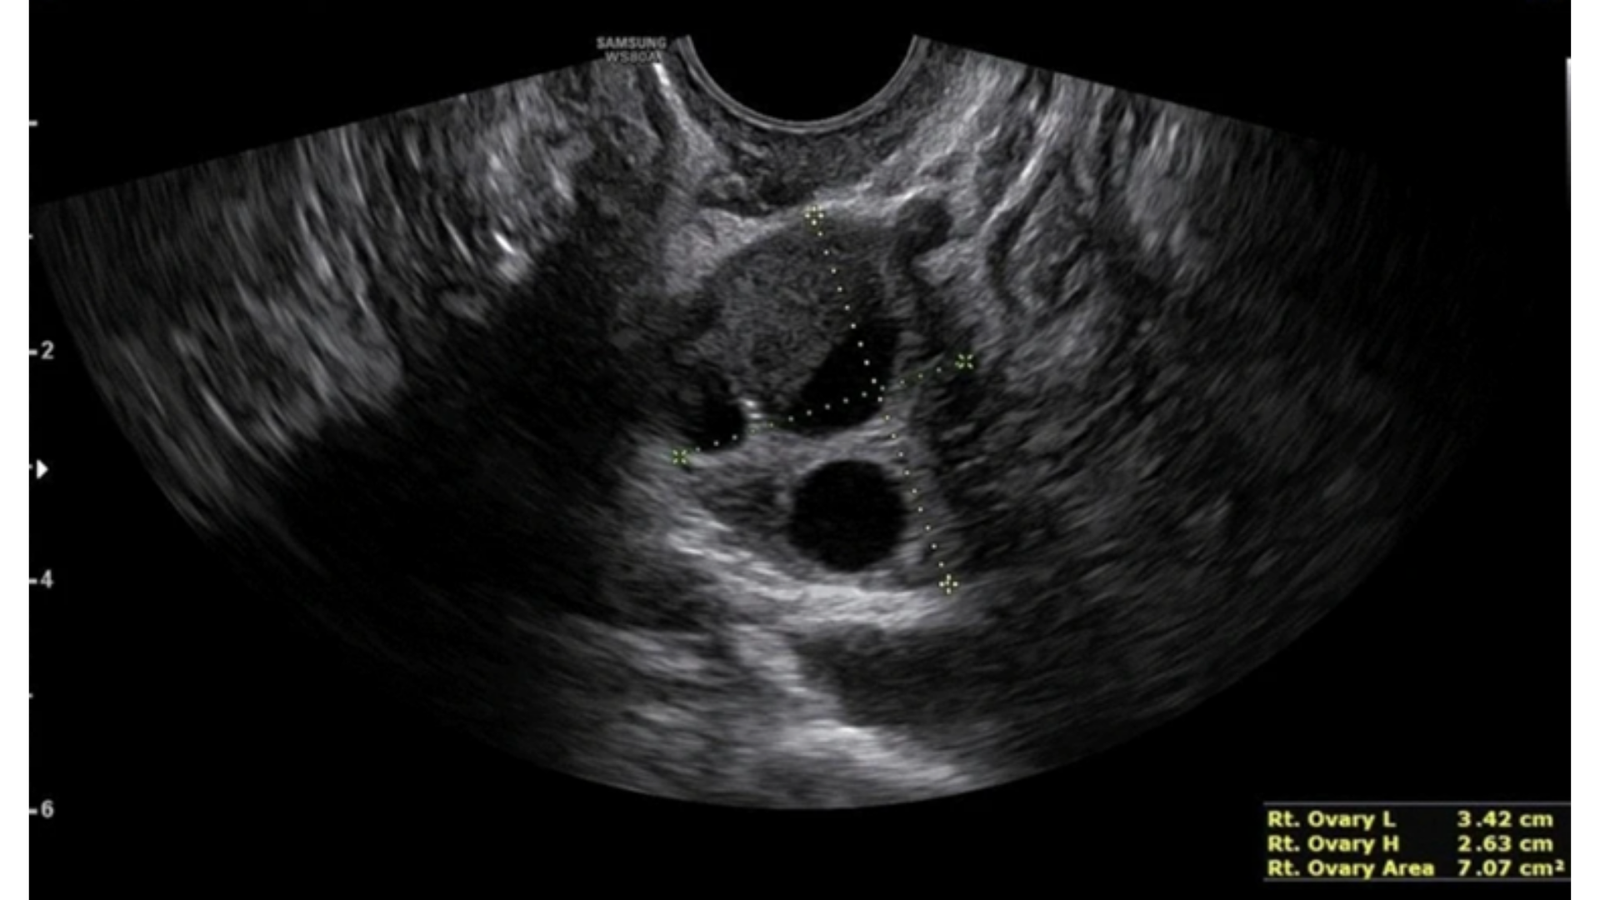

Endometrioma con evidencia del característico doble nivel líquido-líquido

Dentro de la formación, se pueden observar puntos hiperecogénicos, síntoma de acumulación de hemosiderina (fig1).